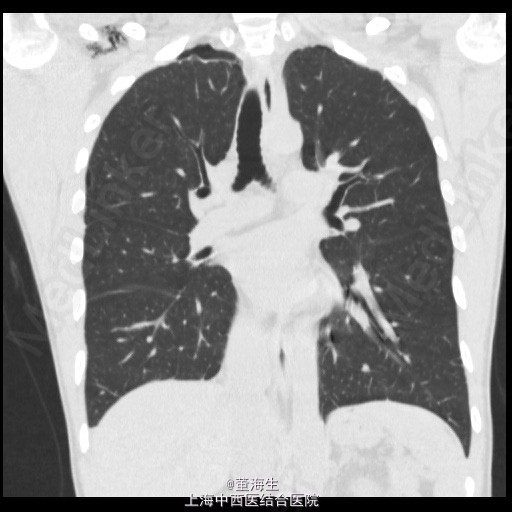

患者,男,39岁。 1.主诉、现病史:患者因为“突发胸闷1日”入院。患者入院当日1:00突觉胸闷,至约16:00来院就诊,辅查胸部CT后如附图1,附图2。既往无类似发作史。 2.查体:患者神清,精神状态良好,生命体征平稳,无气促。右肺听诊呼吸音消失,左侧正常。 3.辅助检查:胸部CT表现如附图1,附图2,血常规提示120g/L,血红蛋白压积正常。 4.诊断:右侧自发性血气胸。 5.处理方案: ①入院后明确诊断,即刻取右侧锁中线第2肋间行胸腔闭式引流。置入8F一次性引流导管一根(该导管头端卷曲,有多个侧孔),导管接水封瓶。静脉给予抗生素及凝血酶,床边心电监护。 ②闭式引流后3小时内引流大量气泡并引流血性液1100ml,即刻复查血常规提示Hgb102g/L。 ③引流3小时后观察引流液不再明显增加,至第二日晨共1400ml血性液,复查血常规仍为102g/L。 ④引流第二日起引流液色逐渐转至浆液性,至入院第6日共引出液体2100ml,负压波动消失,每日引流量少于100ml。予夹闭引流管。 ⑤夹管24小时后复查胸部CT,结果见附图3,附图4。当日予拨除胸腔闭式引流。 6.随访复查:出院后1周,门诊复查胸片及胸水B超,提示无气胸及液胸。 7.分享病例的体会: 实习时老师教导,每小时胸引>200ml血性液,应急诊行剖胸探查。该病例实际治疗时因读片提示胸腔大量积液,保守估计该有1500ml左右,且发病至入院已约15小时,且患者生命体征平稳。故治疗时采取的思路为先放尽积液再计算单位时间内引流量,同时密切观查患者生命体征变化。 此病例没有盲从缺少先决条件的临床条例,免除了患者的手术痛苦。 是否得当请广大同行指正!